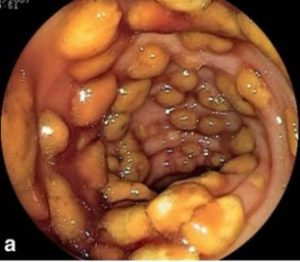

C.Difficiale değişik 2 toksin (toksin A ve B) salgılar, bunlarda bağırsak mukozasında tahribat yaparak ishale neden olur. Dışkıda bunların varlığının gösterilmesi ile tanı konur. %25 vakada tanı konmayabilir. Gaitada bu toksinlerin gösterilememesi hastalığın olmadığını göstermez. Kolonoskopide kalın bağırsak mukozasında psödomembran adı verilen sarı renkli plakların olması tanıya yardımcıdır.